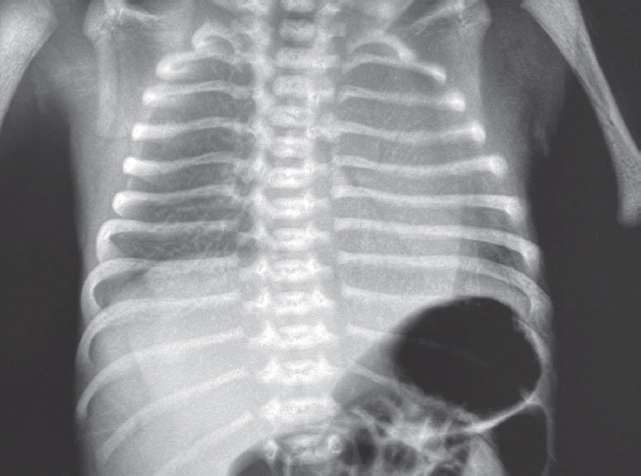

В левый главный бронх повторно введен порактант-альфа. После выполнения манипуляции отмечается клинико-рентгенологическое улучшение (рис. 4) — увеличение SpO2 до 90 %, положительная динамика газового состава крови.

Рис. 4. Рентгенограмма органов грудной клетки новорожденного после повторного монобронхиального введения сурфактанта

Fig. 4. Chest X-ray of newborn after repeated monobronchial administration of surfactant